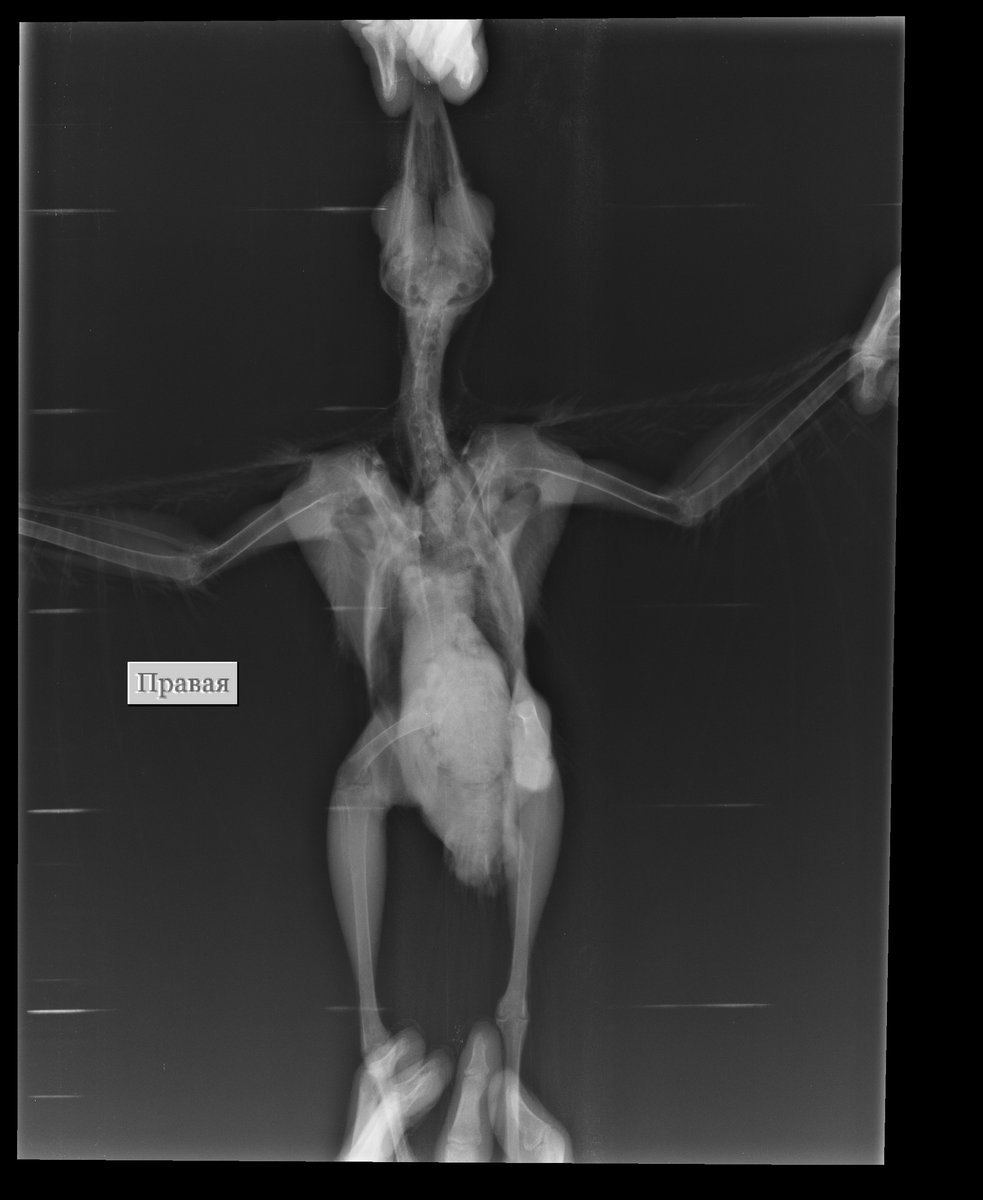

Galastar26 Опубликовано 28 августа, 2020 Автор #6 Опубликовано 28 августа, 2020 (изменено) Спасибо, всем,кто ответил. Видео сюда не грузится (во всяком случае, с компьютера). Вчера были у ветеринара, которая нашла одышку (я ее не замечала), потому и летать не может -- дыхательная система плохо работает. Результаты анализов: 1. Гельминтов у нас не нашли. 2. Простейшие: ооцисты эймерии (средняя степень -- от 1000 до 10 000; это много). 3. Грибки (по помету): кандидомикоза нет; микрогрибки тамнидиум. Ветеринар предположила аспергиллез. Сегодня делали рентген в двух проекциях. На прием только через два дня, поэтому, что там на рентгене, не знаю. Рентгенолог сказала, что ничего не нашла, но врач посмотрит подробнее (через два дня). Пока назначила: 1. Бисептол 120 - по 1/4 таблетки 2 раза в день, курс 5 дней, неделю отдых, потом повторить еще 5 дней. Через 14 дней снова сдать анализы. Но сегодня у птицы идет черная желчь, поэтому дозировку врач уменьшила. Антибиотики давать побоялась. Это от эймериоза. 2. Пирацетам 1 мл 3 раза в день, курс 3 недели. Витамин В1 0,5 мл 1 раз в день с едой, курс 10 дней. Это неврологическое лечение от задержки развития. 3. Немного подкорректировала рацион -- минеральная подкормка (молотая яичная скорлупа). У врача на приеме мы были вчера. А сегодня птенец чувствует себя хуже: желчь, один раз вырвало едой ( это не погадки), проглотить часто не может даже то, что я ему в глотку запихала. Хорошо бы чем-то его поддержать, но ветеринар уже не берет трубку. Может, Карсил купить? Или Гамавит вколоть? Сейчас самое слабое место -- печень. Это из-за эймерии. До понедельника может и не дожить. Изменено 28 августа, 2020 пользователем Galastar26

Galastar26 Опубликовано 28 августа, 2020 Автор #15 Опубликовано 28 августа, 2020 28 минут назад, fishka сказал: Из лекарств даете только Бисептол, Пирацетам и B1? Пирацетам в каком виде? Пока да. Через два дня на прием к врачу по результатам рентгена. Результаты рентгена записаны на СД, Это на другом компе надо открывать. Если получится, выложу здесь.

Galastar26 Опубликовано 28 августа, 2020 Автор #16 Опубликовано 28 августа, 2020 42 минуты назад, fishka сказал: С Аспергиллезом и его лечением тоже не спешите, нужно получить рентген и выложить в тему. Не вижу предпосылок к нему. Сделайте видео одышки. Птица периодически чихает? Как часто? Не чихает совсем. Одышка только тогда, когда сильно крыльями машет. Врач и сказала: потому и не летает, что дыхательный аппарат плохо работает. Ищем причину. Обещали выслать рентген по почте. Тогда смогу выложить.

Galastar26 Опубликовано 28 августа, 2020 Автор #20 Опубликовано 28 августа, 2020 (изменено) @fishka , только что пришли снимки. Не могу судить о качестве и разрешении. Если получится, посмотрите, пожалуйста. По последнему снимку можно сказать, что это мальчик? Изменено 28 августа, 2020 пользователем Galastar26